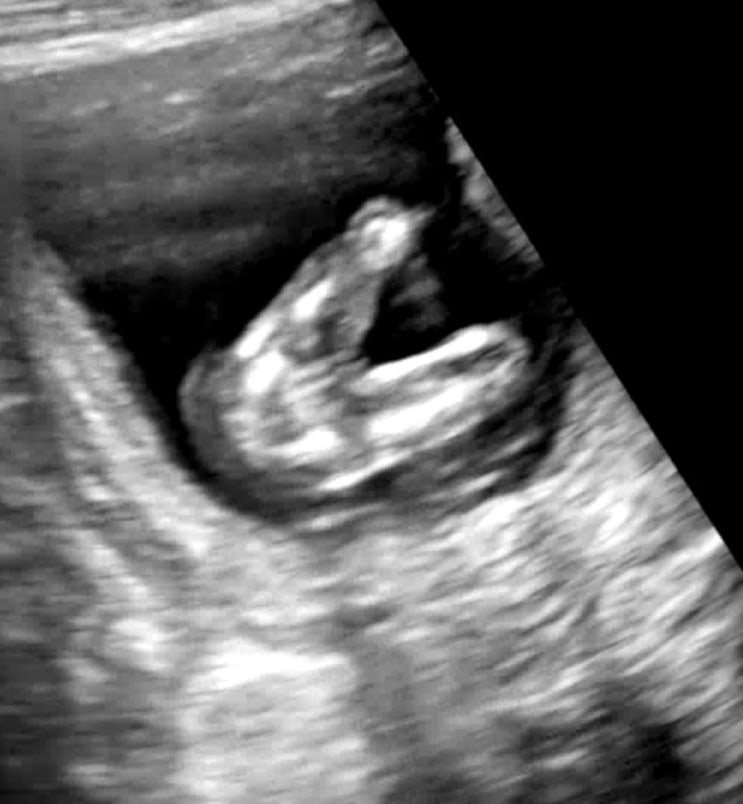

19주 성별 확정, 드디어 나도 딸맘이다

19주, 생리통처럼 아랫배와 허리가 아프고 밑빠짐 통증도 있어서 동네 산부인과에 다녀왔다. 별 일 없겠지...

15주~17주 기형아 검사, 성별 확정?

안정기에 접어들면서 체력도 좋아지고 심적 불안감도 없어져서 평온한 하루하루 보내는 중. 자연스레 블로...

13주6일 두 번째 성별힌트

약 열흘만에 행복이를 보고 왔다.ㅎㅎ 하이베베로 행복이가 잘 있는지를 매일 확인했었는데 14주차쯤 되면 ...

13주 하이베베는 내 일상

#하이베베 #하이베베성공 #임신13주하이베베 #임신13주심박수